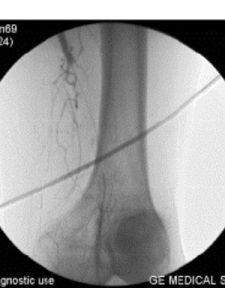

5.動脈造影因動脈造影具有一定危險性和併發症,且並非確診本病所必需的方法,故不列為常規的檢查步驟但對於需要手術治療者則必須做動脈造影,它可以在術前了解動脈阻塞部位範圍、輸出道及側支血管情況,對制訂合適的手術方案至關重要一般通過股動脈插入導管至腹主動脈注入造影劑,但如腹主動脈下端阻塞或兩側髂動脈阻塞者可自上肢肱動脈插管至降主動脈做造影。